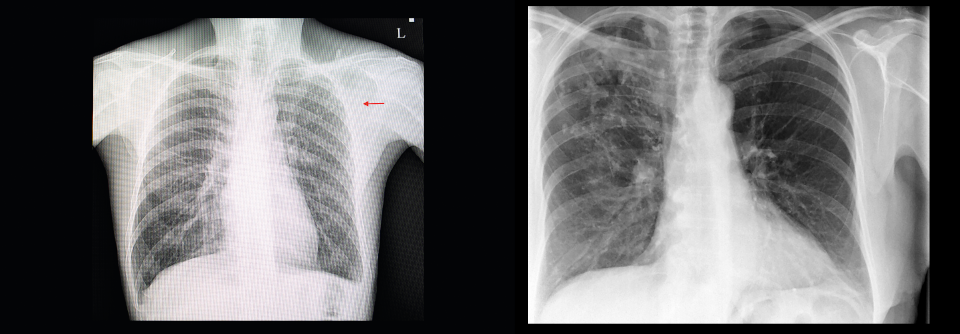

Die Entzündungsmarker im Blut lagen im Normbereich und in der Röntgen-Thorax-Aufnahme zeigten sich nur alte Veränderungen. Auffällig war die Bildgebung des rechten Fußes und des oberen Sprunggelenks: Es imponierten u.a. ausgeprägte Deformierungen und Verkalkungen sowie eine vollständige knöcherne Durchbauung im oberen und unteren Sprunggelenk.